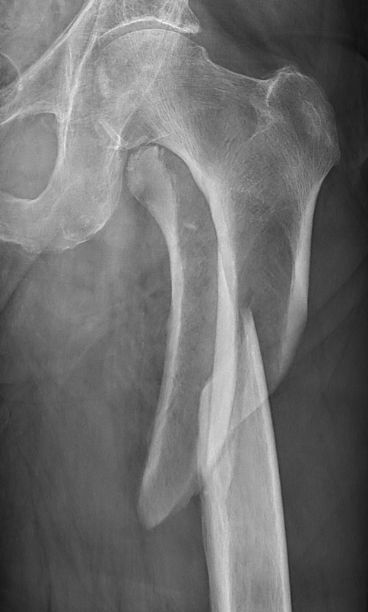

Skada: Fraktur femur diafys

Klassificering

Klassificeras enligt AO: [1]

- 32A (enkel fraktur)

- 32A1: spiralfraktur

- 32A2: sned

- 32A3: tvär

- 32B (fraktur med böjkil)

- 32B2: intakt böjkil

- 32B3: splittrad böjkil

- 32C (splittrad fraktur)

- 32C2: helt segment

- 32C3: splittrat segment